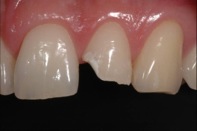

Gãy thân răng không lộ tủy

Nên giảm tác động mạnh trên răng, theo dõi tủy răng và chỉ lấy tủy khi răng bị sưng, đau. Thường sau 3 tuần bị chấn thương, nha sĩ mới thực hiện việc trám tái tạo thân răng.

Gãy thân răng có lộ tủy nhưng không chảy máu

Răng chỉ đau khi bị kích thích, nên đến nha sĩ điều trị sớm bằng thủ thuật điều trị tủy răng.

Trường hợp lộ tủy, chảy máu từ vết gãy, răng chưa đóng chóp đủ, nên đến nha sĩ điều trị tủy và băng tạm ống tủy 3-9 tháng hoặc 1-3 năm, đến khi răng đóng chóp mới trám bít tủy răng hoàn chỉnh. Lưu ý các răng đã lấy tủy rất dễ vỡ nếu va chạm vật cứng. Vì vậy việc cần làm càng sớm càng tốt sau chữa tủy răng là làm mão bọc gia cố cho toàn bộ thân răng và phục hồi lại vẻ thẩm mỹ của vùng thân răng bị gãy, vỡ.